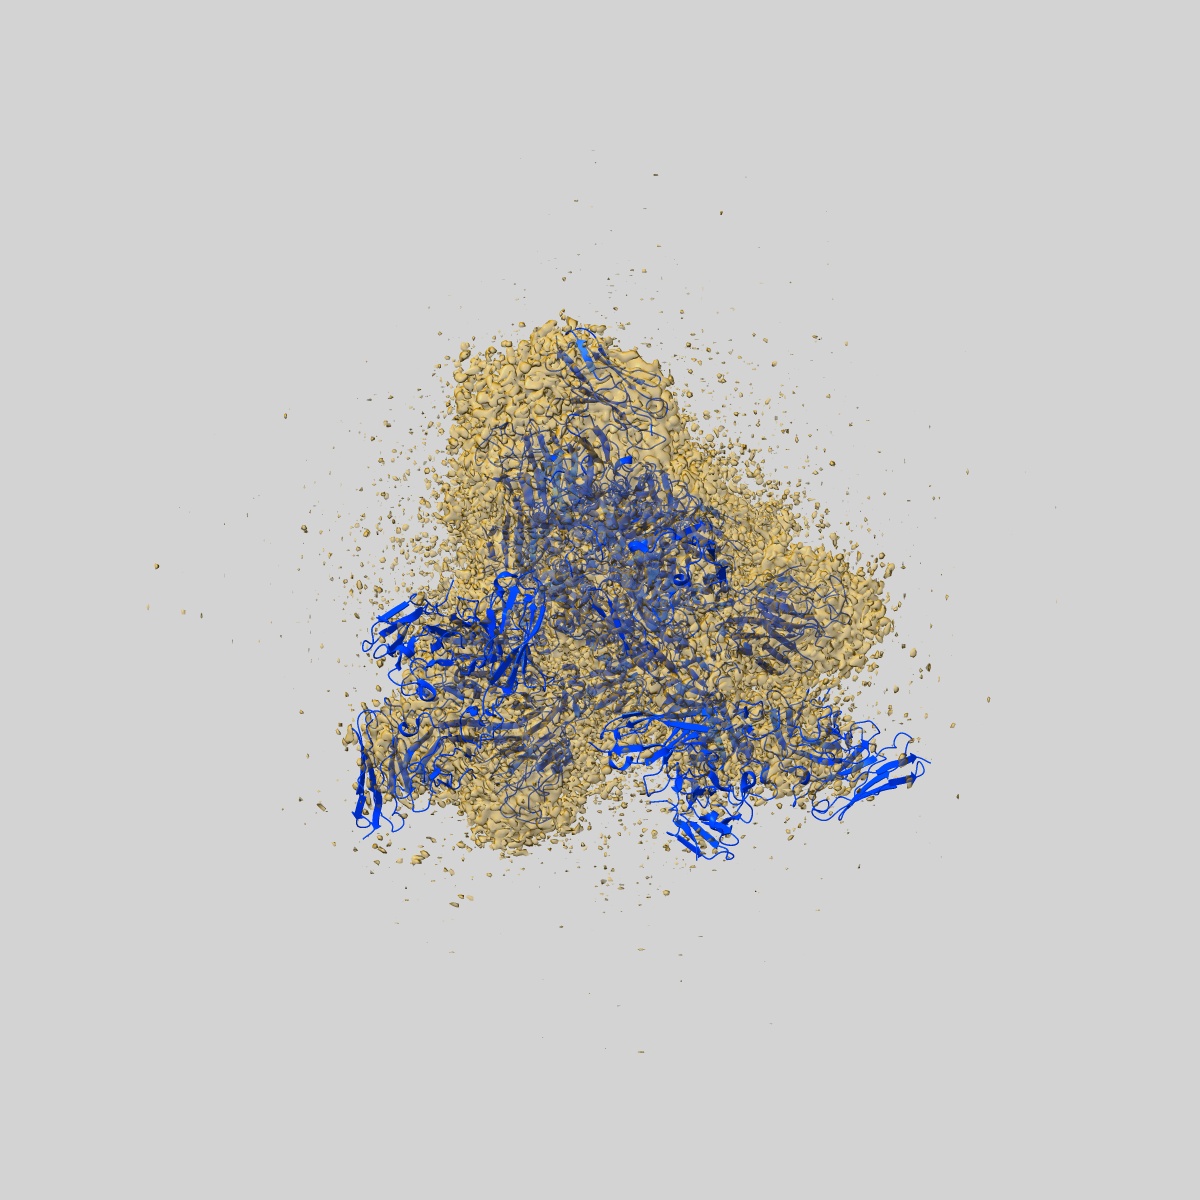

Cryo-EM structure of SARS-CoV-2 Omicron spike glycoprotein in complex with three F61 Fab and three D2 Fab

Single-particle3.04 Å

Sample: SARS-CoV-2 Omicron spike in complex with F61 and D2 Fab

Fitted models: 7xst

Structural basis of a two-antibody cocktail exhibiting highly potent and broadly neutralizing activities against SARS-CoV-2 variants including diverse Omicron sublineages.